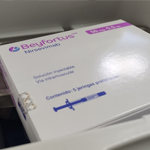

Recién nacidos protegidos contra el VRS en el HGGB

más de 50 han sido inmunizados

Partió vacunación con Nirsevimab contra VRS

para recién nacidos y lactantes menores de seis meses